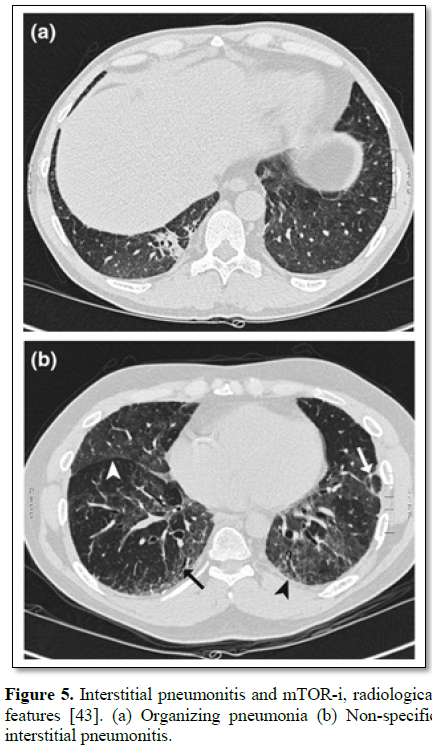

Interstitial pneumonitis (Figure 5) remains rare, but a potentially fatal complication of m-TOR I. In a case-cohort study [43], the incidence of m TOR related pneumonitis remained 12.7%. The pneumonitis is of two main types:

• Multifocal consolidation in the peri-bronchial or subpleural region, compatible with organising pneumonia (OP).

• Extensive bilateral ground glass appearance or airspace consolidation, suggestive of Non-specific interstitial pneumonitis (NSIP).

• Combination of the above.

In every patient, an infective cause should be included before making the diagnosis of drug-induced pneumonitis. Treatment includes cessation of mTOR-I and supportive therapy [43].